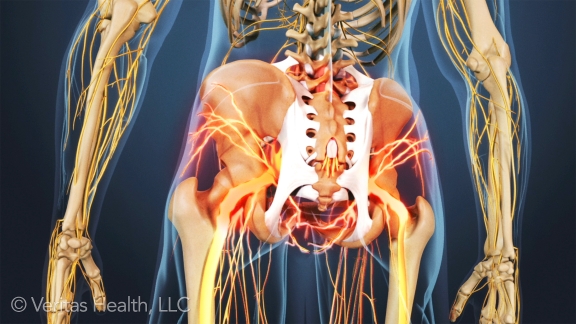

Ankylosing spondylitis (AS) is a type of arthritis that primarily affects the spine. The disease is characterized by inflammation and resulting stiffness and pain in the joints along the spine. The knee and shoulder joints may also be affected.

With ankylosing spondylitis (pronounced ankle-low-zing spond-ill-eye-tis), the inflammation in the joints of the spine will typically result in parts of the vertebrae and joints in the spine fusing together. As parts of the vertebrae grow (or “fuse”) together, the spine becomes more rigid and inflexible.

The fusion takes place as a reaction to inflammation of ligaments or tendons at the site of attachment to bone. The inflammation causes bone to erode at the site of the attachment, and then as the inflammation subsides, the body’s natural healing process causes new bone growths in its place.